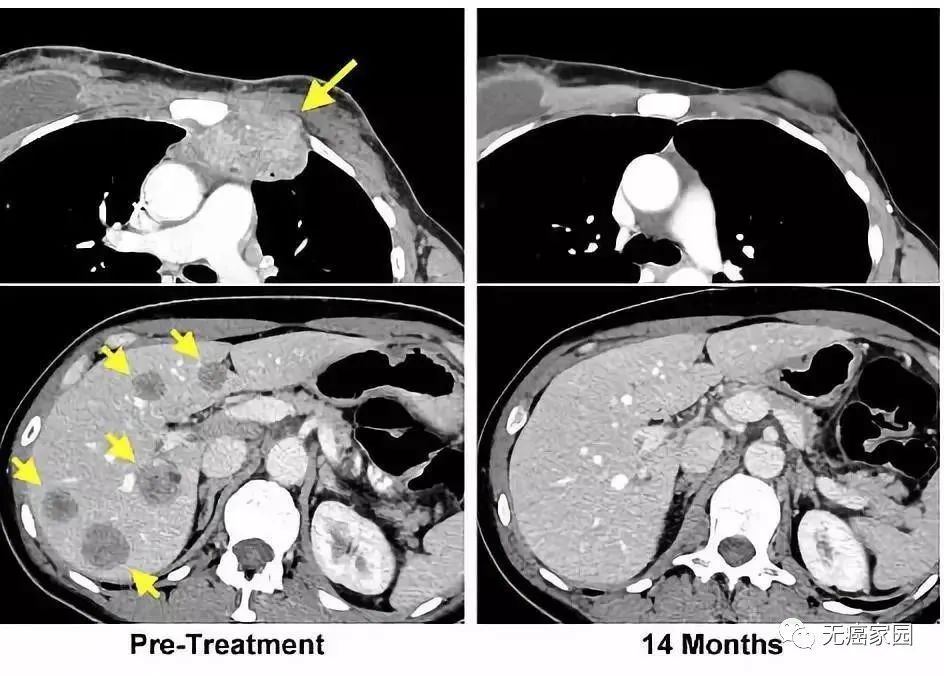

左图黄色箭头是治疗前肿瘤位置;右图是治疗结束14个月后的复查:肿瘤完全消失

CT扫描图(图1位治疗前,图2是治疗4周后,图3位治疗40周后)